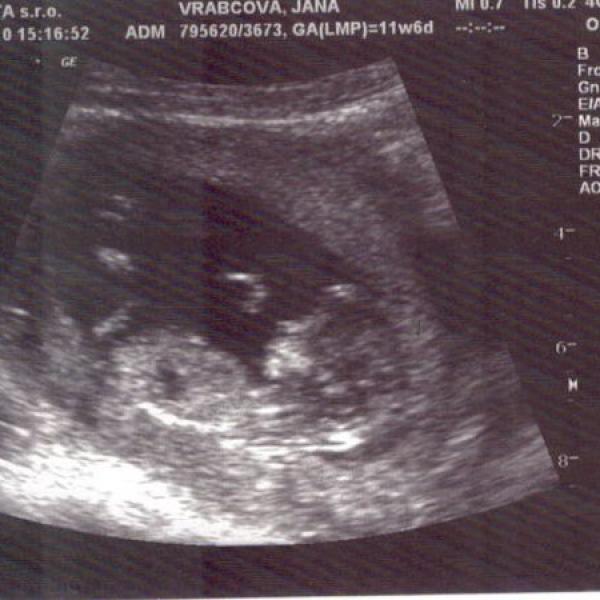

Ahojky :€O: ... tak tady je naše první fotečka :))) krásný den všem :k: :!k:

Milé těhulky ...tak jsem včera byla na kontrole v týdnu 9+0... miminku se daří dobře, bylo krásný ho zase vidět, jak už má krásně viditelné nožičky, ručičky.